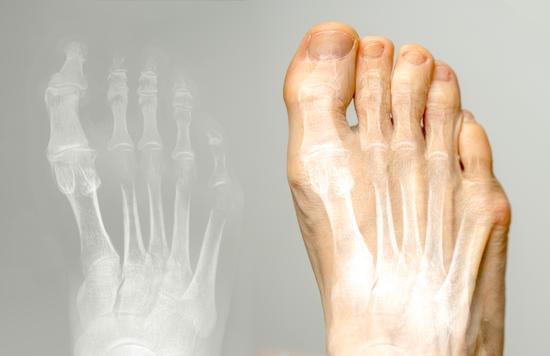

증족골 내반 변형: 원인, 증상 및 치료 방법

증족골 내반 변형은 발의 중족골(발의 뼈 중 네 번째와 다섯 번째 발가락 뼈)을 포함한 발 외측이 안쪽으로 기울어져 변형되는 상태를 말합니다.

증족골 내반 변형은 눈으로 관찰될 수 있는 외형적인 변형 외에도 다양한 증상을 동반할 수 있습니다.

발 외측의 돌출

발 외측이 안쪽으로 기울어지면서 외측이 돌출되어 외형적인 변화가 나타납니다. 이는 육안으로도 확인할 수 있습니다.